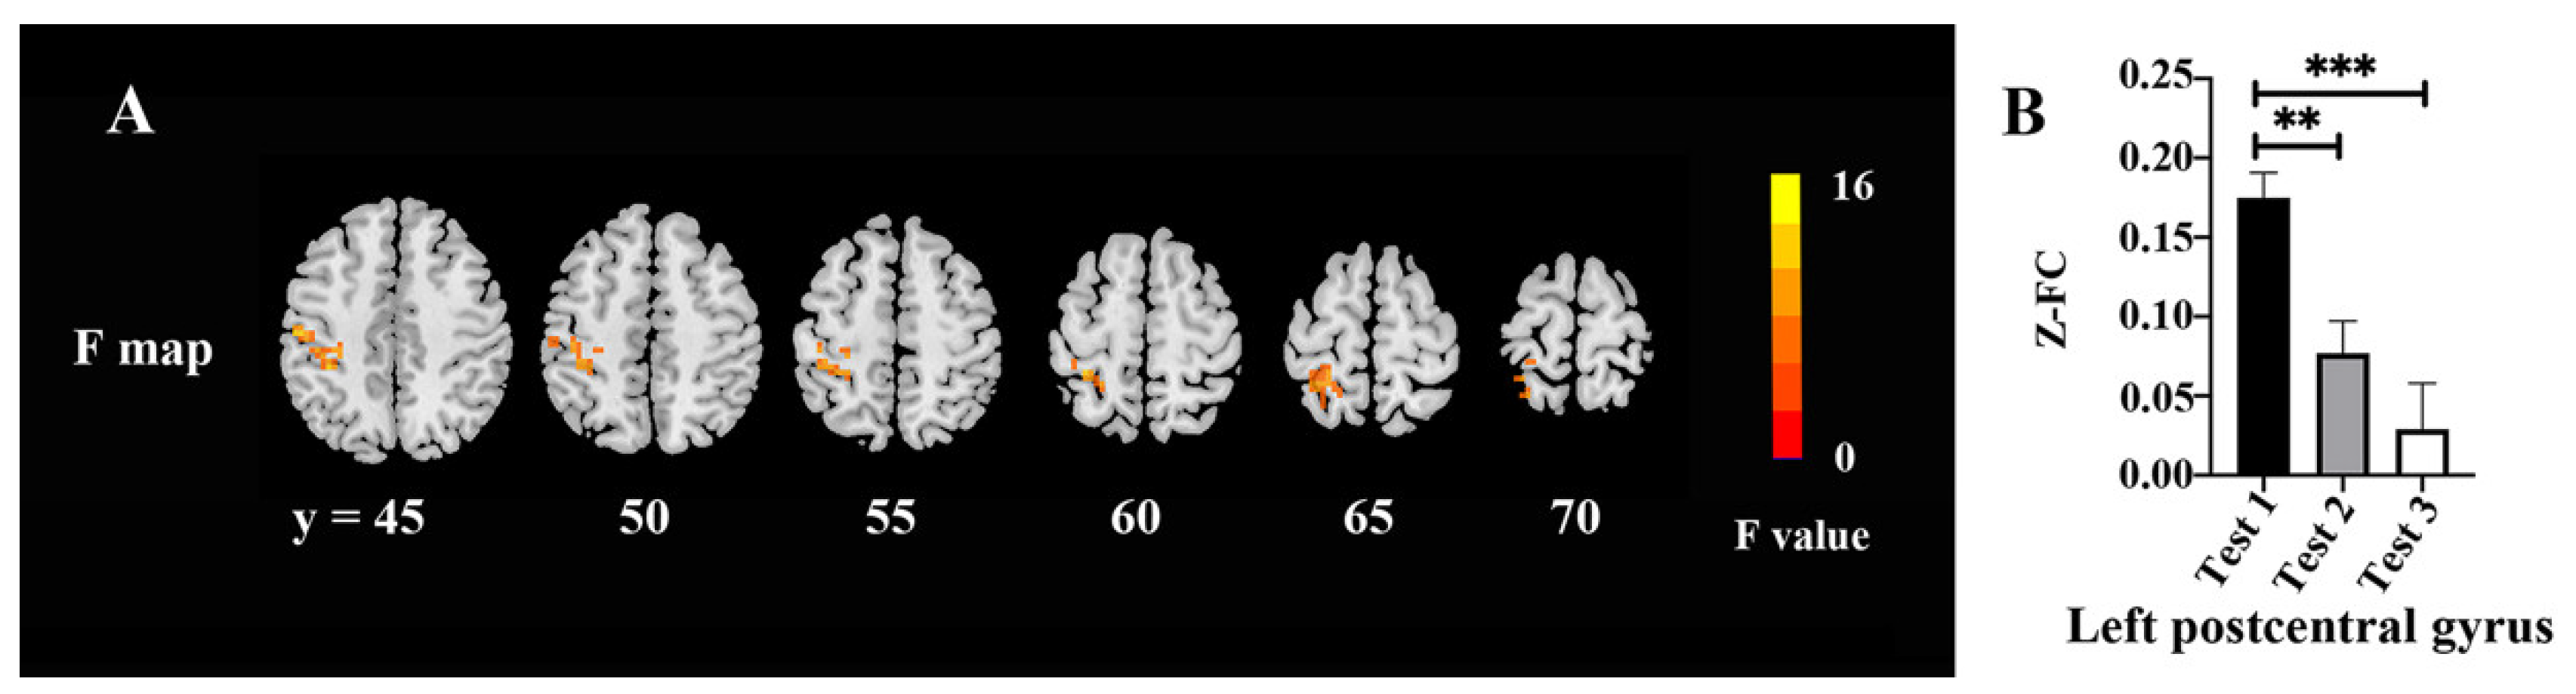

3.6. FC Values

| Area | Broadmann Area | Volume (Voxels) | Talairach | F (Peak) | ||

|---|---|---|---|---|---|---|

| X | Y | Z | ||||

| Postcentral_L | 6 | 174 | −51 | −18 | 45 | 14.23 |